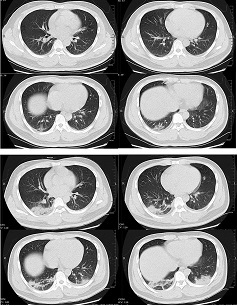

32 წლის მამაკაცის კომპიუტერული ტომოგრაფია განივი ჭრილში; ვლინდება მქრქალი მინისებრი დაჩრდილვა და მარჯვენა ფილტვის ქვედა წილის კონსოლიდაცია პლევრასთან ახლოს. სურათი მიღებულია სიმპტომების გამოვლენიდან 1-ლ დღეს (ზედა პანელი); ორმხრივი მქრქალი მინისებრი დაჩრდილვა და კონსოლიდაცია ვლინდება სიმპტომების გამოვლენიდან მე-7 დღეს

Xu XW et al. BMJ. 2020;368:m606